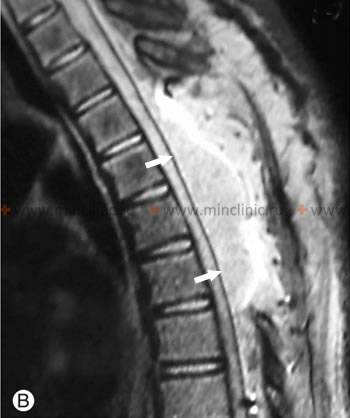

Экстрадуральная гематома на МРТ позвоночника, возникшая у пациента после операции по удалению гемангиомы.

При диагностике спинального кровоизлияния у пациента на миелографии определяется объемный процесс. Компьютерная томография позвоночника (КТ) данную гематому иногда не обнаруживают, поскольку сгусток крови не удается отличить от расположенной рядом костной ткани.